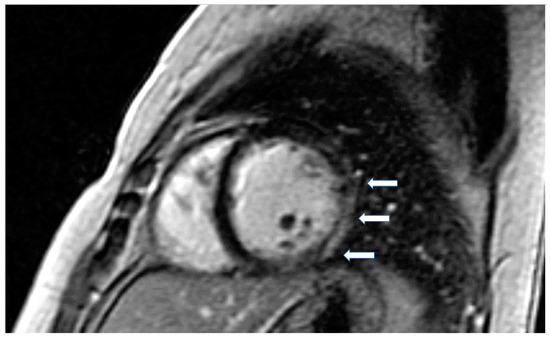

Figure 3.

Short axis LGE image showing diffuse subendocardial fibrosis (arrows) in a patient with Churg–Strauss vasculitis.